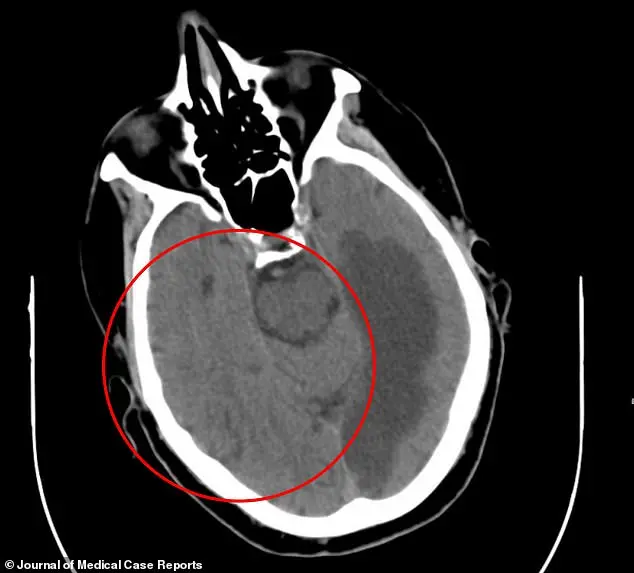

A CT scan of the patient’s brain revealed severe damage to the left temporal lobe, an area critical for language comprehension and memory, and the occipital lobe, which processes visual information.

The damage extended into the corpus callosum, the neural bridge connecting the brain’s hemispheres and essential for coordinating motor functions and sensory processing.

Doctors, writing in the *Journal of Medical Case Reports*, concluded that the stroke had likely triggered AHS by disrupting the brain’s ability to regulate motor control.

This theory aligns with existing research suggesting that AHS often arises from lesions or damage in the corpus callosum, though the exact mechanisms remain a subject of ongoing study.